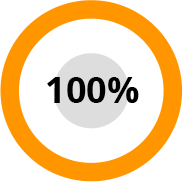

Az ízületi betegségek megelőzésének világszervezeti nemzetközi kutatóközpontok hat hónapon át elvégeztek számos klinikai vizsgálatot és alapkutatást a HondroLife spray készítményen. 2500 önkéntes vett részt a kutatásban.

A tesztek eredményeként kiderült: